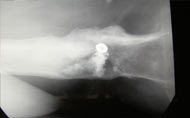

Sept chip